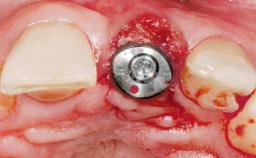

Immediate Placement of an Implant in a Maxillary Left Central Incisor Site

A 33-year-old female patient presented with an upper left central incisor that required extraction after a failed endodontic therapy. The tooth had been traumatized when the patient was a teenager and had undergone several endodontic treatments, including two apicectomy procedures. The patient was in good health and did not smoke. Clinical examination showed that the patient had a high lip line. In full smile, the gingival margins of the upper teeth were visible to the first molars. The gingival margins of central incisors 11 and 21 were only just showing. Examination of tooth 21 confirmed that the tooth was mobile and had hypererupted by 1 mm.

Placement Protocol | Immediate implant placement |

Tooth Site | Maxillary incisor or canine |

Socket Morphology | Single-root socket |

Socket Integrity | Damage to one or more bone walls |